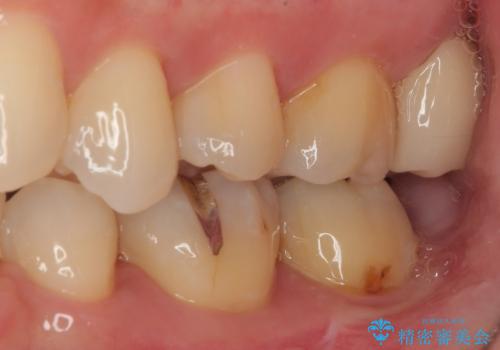

- 元々むし歯があったものの、処置が困難とのことでしたが、矯正治療を終えたので処置をしたいとのことで来院された患者様です。

左右ともに最後臼歯が頬側に顕著に突出しており、むし歯になってしまったことが想像されました。

矯正治療により処置が可能な位置に歯が移動したため、オールセラミッククラウンにて補綴治療を行うこととしました。

歯列が移動したとはいえ、左右ともに後方傾斜しており、むし歯の除去、形成(形を整える)、型取りの全てが非常に困難な処置となりました。